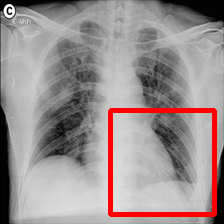

Fig. 7: Medical image segmentation from QaTa-COV19 dataset. The text annotations are created by hand-craft.

QaTa-COV19: This dataset from Tampere University and Qatar University contains 121,378121378121,378 chest X-ray images (CXRs), including 9258 coronavirus disease 2019 (COVID-19) samples. Each image has a corresponding ground-truth mask for COVID-19 pneumonia segmentation. We choose 50 images as our training set and 10 images as our testing set. In addition, we create the text annotations for this datasets.

Fig. 7 shows the results obtained from experiments on the QaTa-COV19 datasets. Closer inspection of the figure shows that MedT has superiority in depicting long-range information. This benefits from the gated parameters. They can control the amount of information that the positional embedding supplies to key, query and value. It is noteworthy that its ability to learn the local features can still be enhanced.

GTUNet still has trouble capturing local features and depicting the exact edge shape. Inferior to GTUNet, SwinUNet can only produce rough infected regions. However, as shown in Fig. 7, it struggles to catch local details, so some incorrect areas are delineated, and the edge depiction is coarse.

UCTransNet and LViT increase their segmented accuracy. We can observe that they depict the correct infected regions of the first and second IMGs in Fig. 7. What stands out in their result pictures is that they cannot give precise edge information.

Compared with other networks, our model integrates Transformer and CNN into PPE, which ensures that it can obtain meaningful representations. After it has these powerful abilities, we combine PPE and the downstream segmentation tasks. Owing to the pretrained phase and the well-designed decoder, our model presents the most exact segmented results.